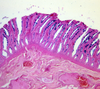

thyroid gland

parafollicular cells

what slide is this?

thyroid

thyroid slide

cuboidal follicular cell